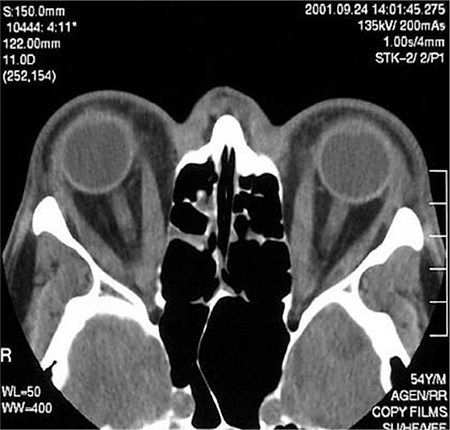

Solicitar exame de imagem transversal da órbita (ou seja, TC ou RNM) em pacientes com orbitopatia unilateral eutireoidiana ou outras apresentações atípicas (por exemplo, nenhuma evidência anterior ou atual de disfunção tireoidiana, ausência de retração da pálpebra superior, estrabismo divergente, manifestação única de diplopia, história de agravamento da diplopia quase ao final do dia); a demonstração de espessamento muscular típico é necessária para descartar outros diagnósticos.[34] Anticorpos antirreceptores de TSH elevados aumentam a probabilidade de o diagnóstico ser uma orbitopatia de Graves, mas esta medida não substitui o exame de imagem orbital se houver suspeita de um diagnóstico alternativo.[3][34][58]

[Figure caption and citation for the preceding image starts]: TC axial através das órbitas de um paciente com orbitopatia de Graves exibindo espessamento elevado dos retos mediaisCortesia do Dr. Petros Perros [Citation ends].